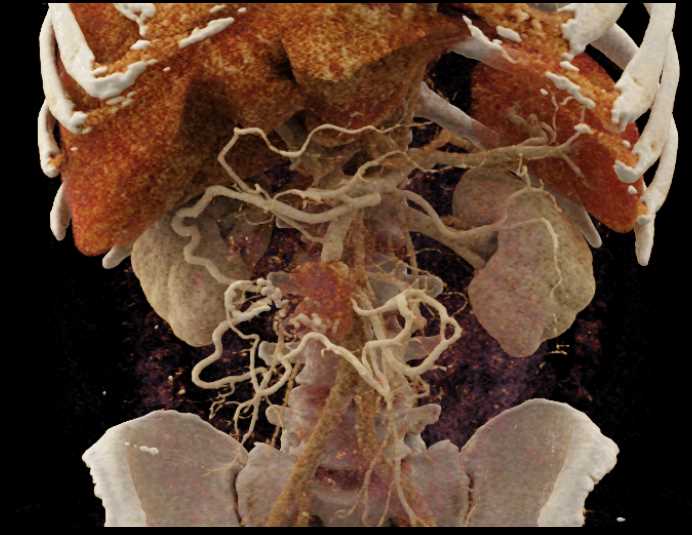

Carcinoid Tumor with Desmoplastic Reaction